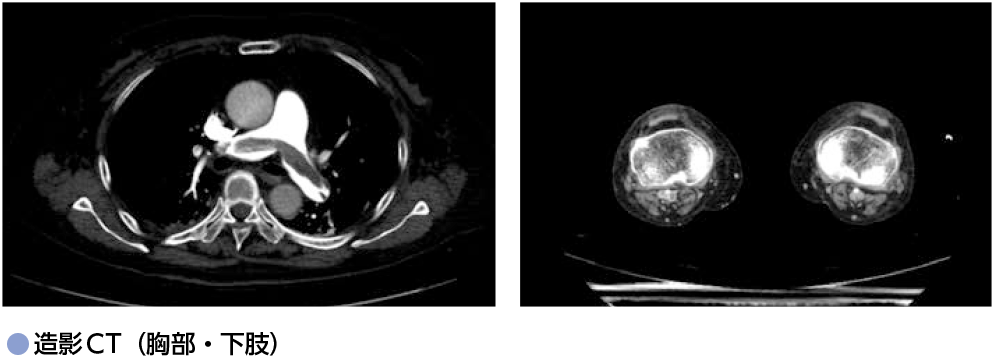

日中起立時の突然の呼吸困難:初診時 初診時 68歳女性.肺癌術後で経過観察をしている.多発神経炎に対してステロイドを内服している.日中は坐位で過ごすことが多い.日中起立時に突然の呼吸困難が出現し,救急車で来院した. 来院時,意識清明,血圧96/71 mmHg,脈拍98回/分,呼吸回数26回/分,SpO2 95%(O2 10 L/分リザーバーマスク)であった.来院時採血では,トロポニンT 0.168 pg/mL,FDP 29.3μg/mL,Dダイマー12.21μg/mL,eGFR 44 mL/分/1.73 m2であった.心エコーでは左室のD-shape様変形を認め,右室の拡大を認めた.造影CT検査を施行したところ以下の通りであった. ※クリック/タップで拡大します 本症例の診断は何か.2つ選べ. ⓐ肺血栓塞栓症 ⓑ急性心不全 ⓒ急性心筋梗塞 ⓓ深部静脈血栓症 本症例に対する初期治療薬として,適切でないものはどれか. ⓐアスピリン ⓑ直接作用型経口抗凝固薬(DOAC) ⓒ未分画ヘパリンナトリウム ⓓワルファリン A1 ⓐ肺血栓塞栓症,ⓓ深部静脈血栓症A2 ⓐアスピリン 重症度評価に基づく治療方針の選択 造影CT上肺動脈主幹部に血栓像があり,右膝窩静脈-大腿静脈に血栓像を認め,肺血栓塞栓症および深部静脈血栓症と診断される(図). 血行動態は保たれているものの,簡易版PESI≧1(表1),右室機能不全と心筋逸脱酵素の上昇を認め,重症度クラスは中[高]リスク(表2)に該当する. 中[高]リスクの症例に対しては,抗凝固療法を第一選択とするが,経過中に血行動態が不安定化する可能性に注意し慎重なモニタリングを要する.血行動態の悪化時は血栓溶解療法を考慮する. 現在のガイドライン1)上,血栓溶解療法の適応は,ショックや低血圧が遷延した重症例のみである.モンテプラーゼ(点滴静注:13,750~27,500単位 /kg,2分間で静注)が使用可能である. ワルファリンを投与する場合は,投与開始から治療域にコントロールされるまで未分画ヘパリンナトリウムを併用する. DOACは即効性があり(抗凝固作用の発現まで1〜4時間程度),ショックのない症例では通常DOACが第一選択として使用されることが多い. 経過観察中に血栓溶解療法を使用する可能性が高いと予想される症例では,半減期が1時間と短い未分画ヘパリンナトリウムが使用しやすい. 文 献 日本循環器学会,他:肺血栓塞栓症および深部静脈血栓症の診断,治療,予防に関するガイドライン(2017年改訂版)(2021年11月閲覧) Konstantinides SV, et al:2014 ESC guidelines on the diagnosis and management of acute pulmonary embolism. Eur Heart J, 35:3033-3069, 3069a, 2014 (2022/06/03公開) 戻る この"ドリル"の掲載書をご紹介します 循環器薬ドリル 薬剤選択と投与後のフォローも身につく症例問題集 池田隆徳/監,阿古潤哉/編 定価:4,950円(本体4,500円+税) 在庫:あり 月刊レジデントノート 最新号 次号案内 バックナンバー 連載一覧 定期購読案内 定期購読WEB版サービス 定期購読申込状況 レジデントノート増刊 最新号 次号案内 バックナンバー 定期購読案内 residentnote @Yodosha_RN その他の羊土社のページ ウェブGノート 実験医学online 教科書・サブテキスト 広告出稿をお考えの方へ 広告出稿の案内